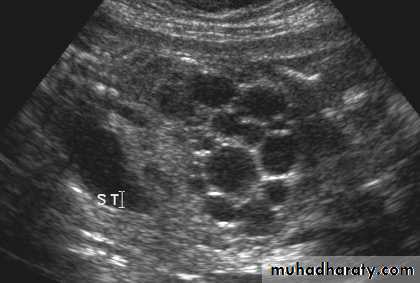

Congenital cystic kidney (polycystic kidney) (Adult cystic renal disease)

Autosomal dominant, transmitted by either parents, 50% of offspring affected.

Both kidneys replaced by large no. of cysts of variable size which make the kidney of large size.

The cysts contain clear fluid but sometimes blood.

The cysts progressively increase in size causing pressure atrophy of the renal parenchyma and pressing the ureter.

15% associated with cystic disease of liver, lung, pancreas or spleen.

Clinical pictures:

Rarely gives clinical manifestation before 4o years

Asymptomatic: diagnosed accidentally.

Pain: due to pedicle stretching, stone, ureteric obstruction, bleeding inside cyst or infection.

Hematuria: cyst distention and rupture to the collecting system.

Infection: renal or cyst infection causes fever, rigor and loin pain.

Hypertension: in 70%, Unknown cause.

Renal impairment: anorexia, headache, nausea, vomiting, drowsiness and coma.

Renal enlargement: large knobby palpable kidney

Diagnosis: Family history of polycystic disease.

U/S, IVU, CT scan, MRI